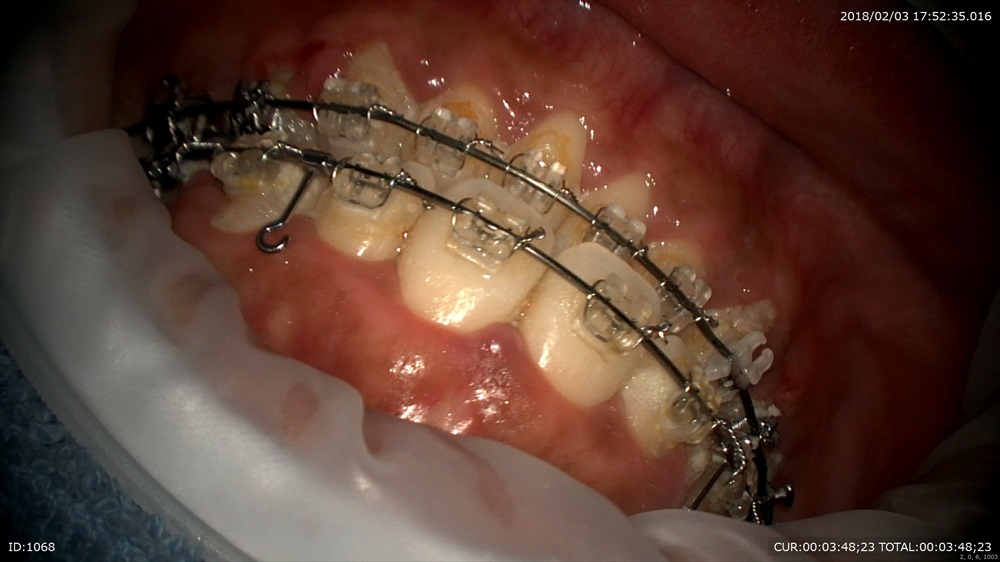

今日最後の患者さまは矯正治療

フィニッシィングステージ

犬歯が甘いので オフセットを。

この様にマイクロスコープを使用して無痛かつ丁寧な治療が当院では可能です。埼玉、八潮、草加、三郷で矯正治療ならBiVi歯科・矯正歯科まで。